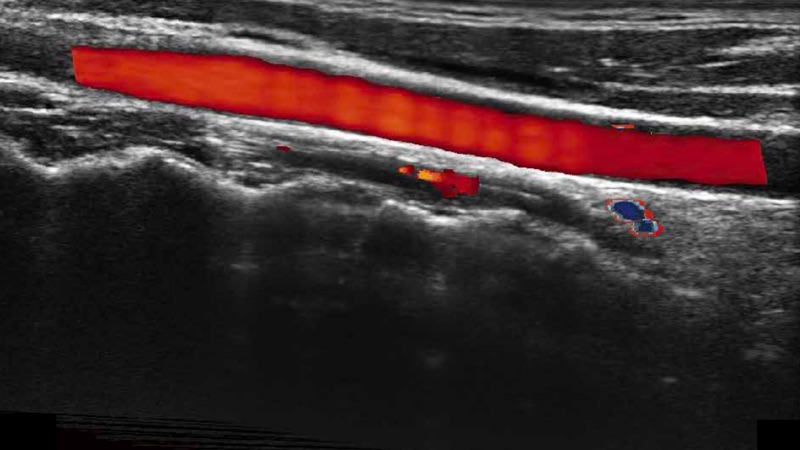

高分辨率血流成像技術(shù)提高了對(duì)低速血流信號(hào)的檢測(cè)能力。在提高空間分辨率的同時(shí),也克服了血流外溢現(xiàn)象,為用戶提供更加真實(shí)的血流動(dòng)力學(xué)信息。

通過色彩血流和實(shí)時(shí)寬景相結(jié)合,可觀察到完整的靜脈或動(dòng)脈的血流,方便醫(yī)生檢查。實(shí)時(shí)掃查過程中,如有任何操作失誤也可以很容易地進(jìn)行回掃擦除,而不會(huì)中斷掃查。